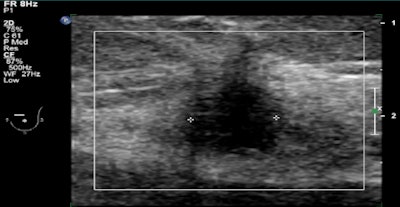

| Mediolateral oblique (MLO) views of a 56-year-old woman whose sister had breast cancer are normal (above). But automated breast ultrasound (below) showed a small mass in the left breast. This image is from a focused breast ultrasound exam, performed because of the finding detected on automated ultrasound. Biopsy confirmed a 10-mm invasive ductal carcinoma. All images courtesy of Dr. Judy Dean. |